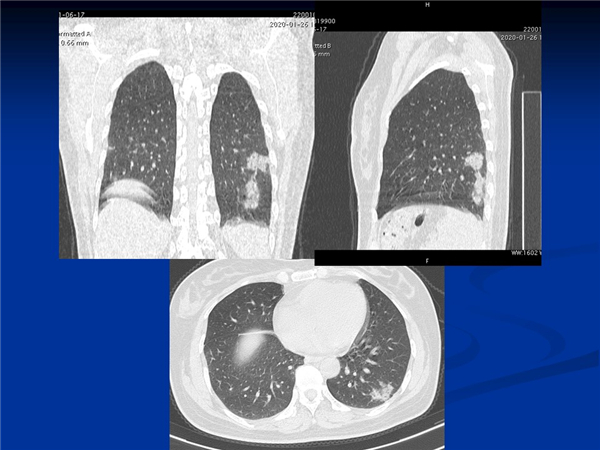

【病例分享】新型冠狀病毒感染肺部CT影像4例(常德市第一人民醫(yī)院)